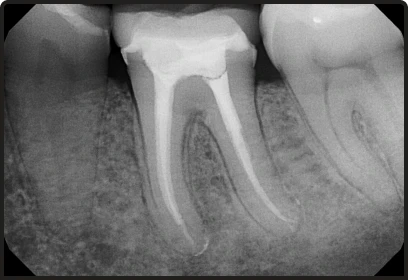

- We utilize digital imaging and rotary endodontics to provide more precise results and faster recovery times.

Root Canal Therapy

The standard therapeutic procedure to remove infection from the tooth’s pulp

- Focuses on immediate pain relief and root canal cleaning.

- Ideal for teeth with enough healthy structure.